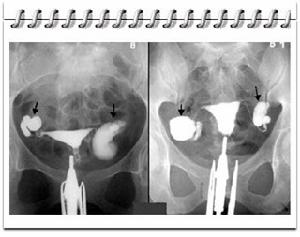

4.用可吸收性造影劑做食管造影,確診率為90%~95%,有5%~10%的的假陰性。因此,陽性結果(看到造影劑溢出食管管腔),但陰性結果不能排除SRE(圖22)。碘化油有一定黏稠度,可以用泛影葡胺作造影劑,讓病人分別採用左、右和平臥位三種姿式造影,增加瘺口顯示的機會。

3.傷在頸段食管時,頸部側位X線片可顯示頸後間隙陰影增寬及皮下氣腫。傷在胸內食管時可見縱隔氣腫或伴有液氣胸,口服碘油可見造影劑逸出食管腔外進入縱隔或胸膜腔,有縱隔炎時可見縱隔陰影增寬。